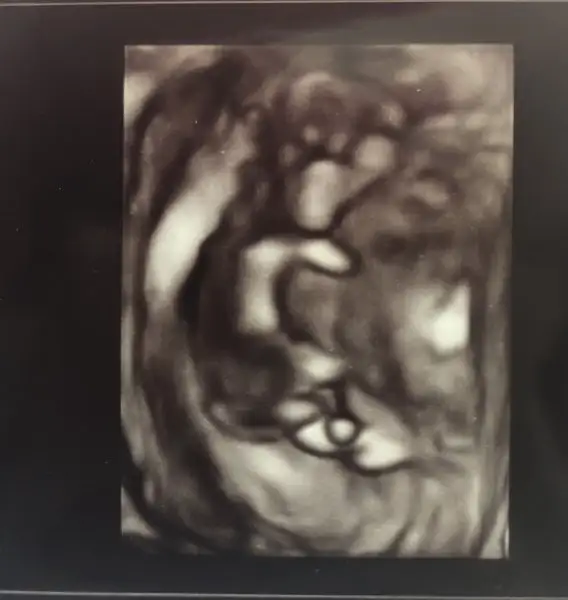

İlk resim 4 boyutlu denilen ultrason(4. Boyut zaman ama olsun :D)